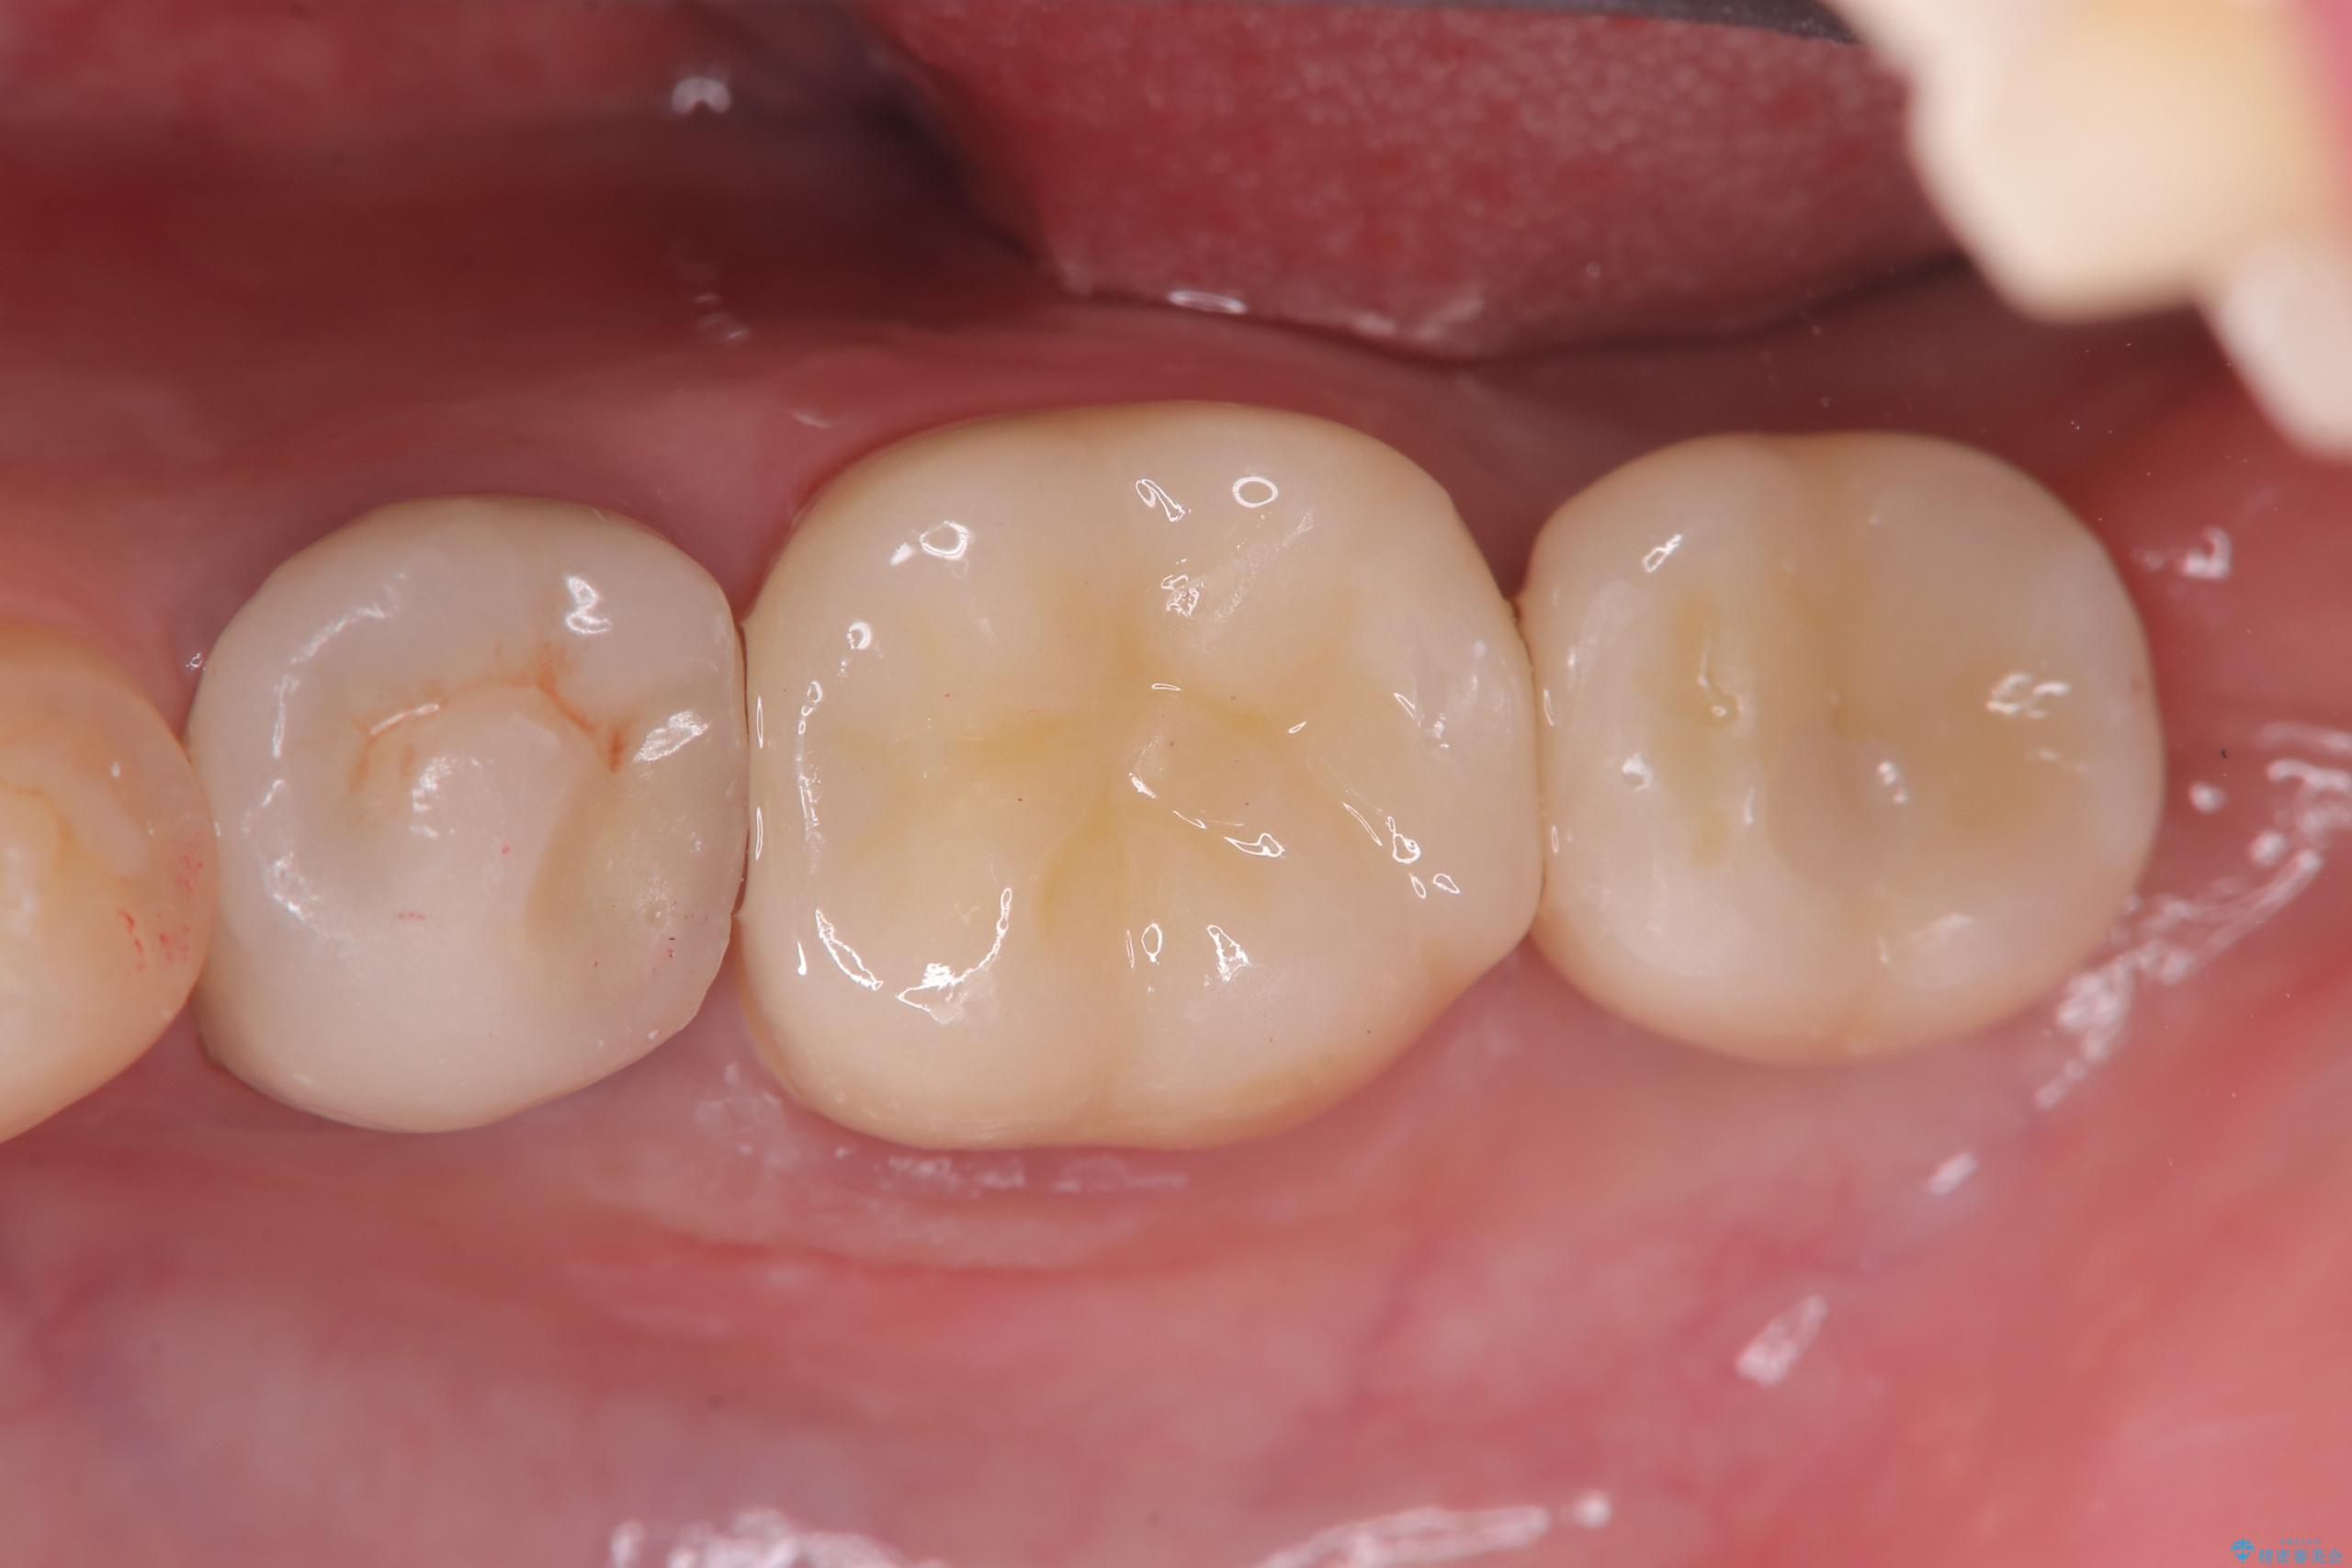

保存は困難と判断し、左下7番は抜歯即時インプラントによる治療を行いました。

また、左下6番には形態が不自然で適合不良のセラミックインレーが装着されていたため、二次カリエスのリスクを考慮し、オールセラミッククラウンによる治療を行いました。

抜歯と同時にインプラントを埋入するため、歯茎を切開する必要がなく、術後の痛みが出にくい治療方法です。

手術は1回で完了し、被せ物を装着するまでの治療期間も約3か月と、身体的・時間的な負担を抑えることができます。